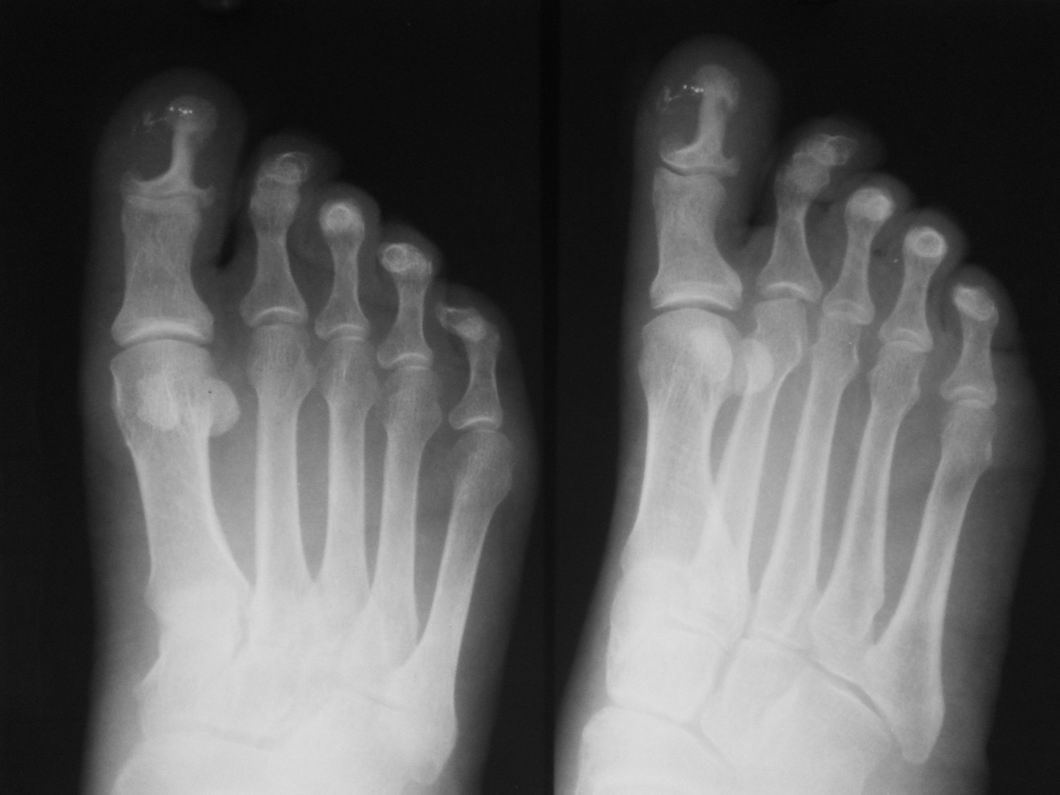

标题: X1349:[原创]男五十岁,,母趾胀痛二十余年,,来院外科医生 [打印本页]

左母趾末节呈哑铃状改变,边缘光滑,残存骨除密度略增高外,无明显破坏征象。内前方见少许小点状高密度影,可能为外来物重叠所致。

考虑:左母趾末节良性病变,可能来源于软组织肿瘤压迫所致(血管球瘤?)。

左母趾末节呈哑铃状改变,边缘光滑,残存骨除密度略增高外,无明显破坏征象。内前方见少许小点状高密度影,可能钙化影。

考虑1血管球瘤。2皮样囊肿